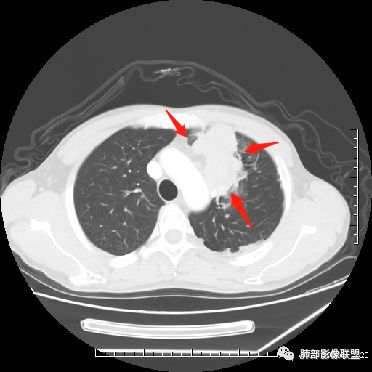

左上肺占位支气管阻塞伴肺不张、肿瘤不均匀强化,考虑鳞癌.

左肺上叶见实性结节,边缘可见分叶,周周可见磨玻璃影,病灶不均匀强化,中心可见坏死,部分坏死边界不清,部分呈环形,血管进入病灶内部,边缘逐渐变细截断,总体表现考虑恶性,腺癌。

中年男性,咳嗽咳痰一月。左肺上叶团块状软组织密度影,边缘部分清晰周围见磨玻璃影,增强后其内密度不均可见散在斑片状低密度区,血管造影征完整,团块邻近胸膜可见多发圆形低密度透光灶。左肺门处上叶血管似被包绕。左侧胸膜粘连肥厚。考虑1.左肺占位,淋巴瘤?鳞癌?2.因病灶内散在低密度待除外感染性病变可能

中年男性,咳嗽咳痰一月余入院胸CT:左肺上叶前段占位性病变,病灶内可见密度不均,可见低密度区,病灶可见分叶,增强病灶内可见血管征,血管边缘模糊,病灶近胸膜下呈膨胀性生长。诊断考虑:恶性病变。

40岁以上男性,中等病程,咳嗽,咳痰,左上块影,孤立,膨胀,胸膜受累,内密度高低不一,血管穿入,考虑肺癌,鳞?气管镜or穿刺!

左肺上叶肿块,强化不均匀,内见坏死,血管纤细,病灶周围有阻塞性炎,所见图像未见肿大淋巴结。考虑鳞癌可能大。

中年男性,亚急性起病,咳嗽,咳痰,左肺上叶肿块,边界清,膨隆,可见分叶,增强可见内部坏死,不均匀强化,部分边界累及胸膜,考虑恶性。

左肺上叶肿块,周周可见磨玻璃影,不均匀强化,内部可见坏死,部分坏死边界不清,血管进入病灶内,恶性肿瘤,考虑鳞癌。

分叶,破坏力不强,纵隔胸膜受累,周围阻塞性炎症,胸膜多发结节。考虑恶性,支持腺癌可能大。

左肺上叶肿块,边缘大部分平直,部分膨隆,周周可见磨玻璃影,不均匀强化,内部可见坏死,部分坏死边界不清,考虑恶性肿瘤,鳞癌可能大,病灶边缘大部分平直,不除外炎性。

患者中年男性,咳嗽、咳痰1月余入院。胸部CT:左肺上叶尖段近胸膜下肿块占位灶,边缘光滑,边界清楚,周围可见片状磨玻璃影,可见平直、毛刺、分叶征象,增强轻度强化,内可见点片多发低密度区及部分血管影,与支气管关系欠清,左肺上叶背侧胸膜增厚、胸膜下结节,右肺似见多发小结节灶,淋巴结不大。综合考虑良性病变,结核可能性大,鉴别腺癌并肺内、胸膜转移及淋巴瘤等。

左肺上叶见不规则肿块影,可见分叶,边缘膨隆部分边缘平直,增强后病灶可见不均匀明显强化,内见血管影,其血管边缘不光滑,周围肺野可见小结节病灶,考虑恶性病变,肿块与支气管关系显示不清,需要薄层,从肿块边缘平直来看应该有阻塞性肺炎和肺不张,偏向鳞癌。

胸CT:左上叶前段团块影,边缘部分清晰,近纵隔侧膨隆明显,分叶,肺侧见平直征,U形凹陷,病灶周围可见磨玻璃影,气肿带,纵隔多发淋巴结肿大,叶间裂多发小结节。增强病灶内密度不均,散在斑片状低密度区,血管造影征。考虑:恶性,鳞?腺?大细胞?鉴别:炎症。似有左侧胸廓内A供血病灶,SFT?

男,47岁,咳嗽咳痰一月余入院肺气肿背景。左上肺纵隔旁非均质肿块,分叶、膨隆,部分边缘光滑,肺门可见冰冻征,增强不均匀强化,见沼泽地样坏死,邻近肺组织见斑片状炎症,考虑恶性肿瘤,首先考虑小细胞癌,鉴别鳞癌。

47岁男性,咳嗽咳痰1月余。左肺上叶结节灶,形态不规则,边缘见分叶,其内可见斑片状低密度区。增强扫描呈轻度强化,侵犯纵隔及部分胸膜,综合考虑恶性!

中年男性,左肺上叶肿块、片状状影,形态不规则,边缘见分叶及磨玻璃影,其内可见斑片状低密度区及血管穿行。增强扫描呈轻度强化,侵犯纵隔及部分胸膜,纵隔见多发淋巴结肿大,定位:肺内,左上肺部分有不张;定性:偏恶性,侵犯支气管(病灶内见条状低密度影)但血管无明显受累,考虑粘膜相关性淋巴瘤(粘膜下起源)可能,结核待排;腺癌、鳞癌(血管无受侵不首先考虑),小细胞(无典型表现、虽然血管保留可见于小细胞);

外大内小,不除外结核。

首先定位肺内,理由是内乳动脉未见移位。左肺上叶前段肿块,边界清楚,边缘呈分叶状,增强扫描呈不均匀强化,内见边界不清无强化坏死区。同时于病灶内见多发迂曲走形边缘毛糙血管影。考虑恶性,建议穿刺。

左肺上叶不规则软组织肿块,分叶,病灶内密度不均匀,周围可见磨玻璃影,外侧可见局限性肺气肿,增强后轻度强化,病灶内强化血管增粗且模糊,坏死区无强化,纵隔淋巴结肿大,考虑恶性占位,鳞癌。鉴别结核。

男,47岁,咳嗽咳痰一月。病灶位于左内乳动脉内缘,定位肺内,呈团片状异常密度影,整体沿支气管气管束走形分布,由肺门达胸膜下,于近肺门侧病灶形态相对较小,病灶远端相对较大,病灶整体密度偏均匀,强化偏明显,病灶内见多发支气管扩张并粘液栓形成,且扩张支气管粗细不均,直达病灶以远,病灶内血管走形正常、粗细均匀,病灶周围见边缘模糊磨玻璃及少许腺泡结节。左肺门及纵隔略大淋巴结,左侧胸膜局限性增厚。诊断:左肺上叶前段异常密度影,炎性肉芽肿性病变可能,结核不能除外,建议穿刺活检除外恶性肿瘤。